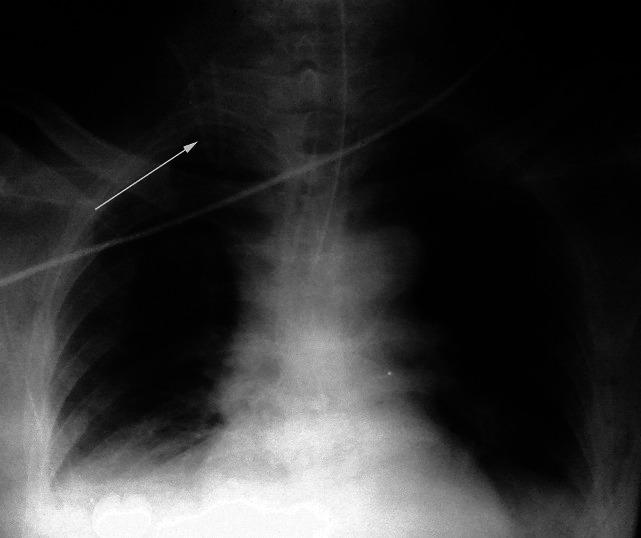

Folding back of central venous catheter in the internal jugular vein: Methods to diagnose it at the time of insertion?

Indian J Anaesth. 2013 Jan;57(1):104-5. doi: 10.4103/0019-5049.108600.

Folding back of central venous catheter in the internal jugular vein: Methods to diagnose it at the time of insertion?颈内静脉中心静脉导管折返:插入时的诊断方法?